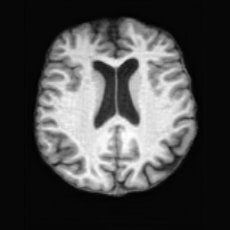

Healthy w/Lesion MaskPathologicalDifferencew/o LCGw/ LCG(a)Refer to captionRefer to captionRefer to captionRefer to captionRefer to captionRefer to captionHealthy w/Lesion MaskPathologicalDifferencew/o LCGw/ LCG(b)Refer to captionRefer to captionRefer to captionRefer to captionRefer to captionRefer to caption

Figure 7: Ablation study of Lesion Consistency Guidance (LCG). Without LCG, the generated pathological regions are indistinct and show weak pathological expression in both examples.

Lesion Consistency Guidance. Fig. 7 illustrates the impact of Lesion Consistency Guidance (LCG) for healthy-to-pathology editing. Without LCG, the generated lesion regions appear blurry around lesion boundaries, and the pathological patterns are less distinct, resulting in ambiguous lesion localization and weak pathological expression. Incorporating LCG produces lesions with more precise localization and well-defined shapes that better align with the given lesion masks, as well as textures and contrasts that exhibit stronger pathological characteristics. These results demonstrate that LCG effectively enforces lesion-aware conditioning, enhancing both spatial and semantic consistency of the generated pathological regions.